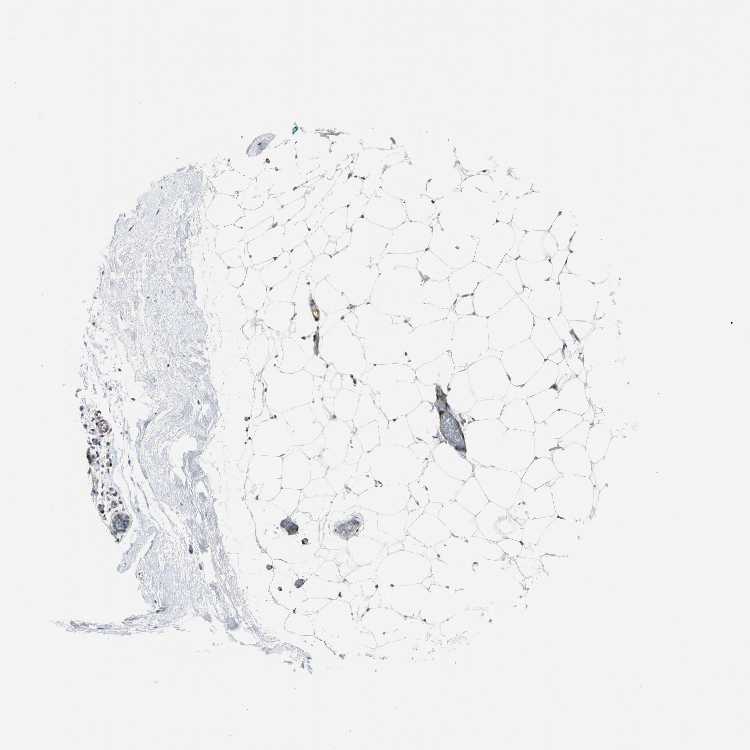

TISSUE PRIMARY DATA BREAST Show tissue menu

BREAST - Antibody stainingi

Antibody staining in the annotated cell types in the current human tissue is reported as not detected, low, medium, or high, based on conventional immunohistochemistry profiling in selected tissues. This score is based on the combination of the staining intensity and fraction of stained cells.

Each image is clickable and will lead to virtual microscopy that enables deeper exploration of all samples and also displays staining intensity scores, fraction scores and subcellular localization as well as patient and tissue information for each sample.

Antibody HPA005922Antibody HPA006028Antibody CAB008368

Adipocytes LowNot detectedNot detected

Glandular cells LowNot detectedNot detected

Myoepithelial cells MediumMediumLow